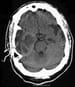

Magnetic resonance spectroscopy is representative of a glioblastoma multiforme.